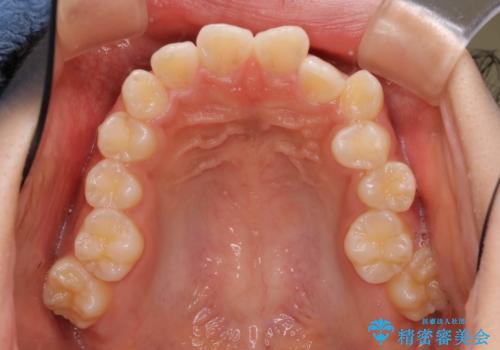

- 上下左右4本の第1小臼歯を抜歯する、抜歯矯正を計画した。

抜歯矯正により前歯の位置が後ろに下がり、わずかではありますが、口元に改善がみられ、歯並びもきれいに整いました。